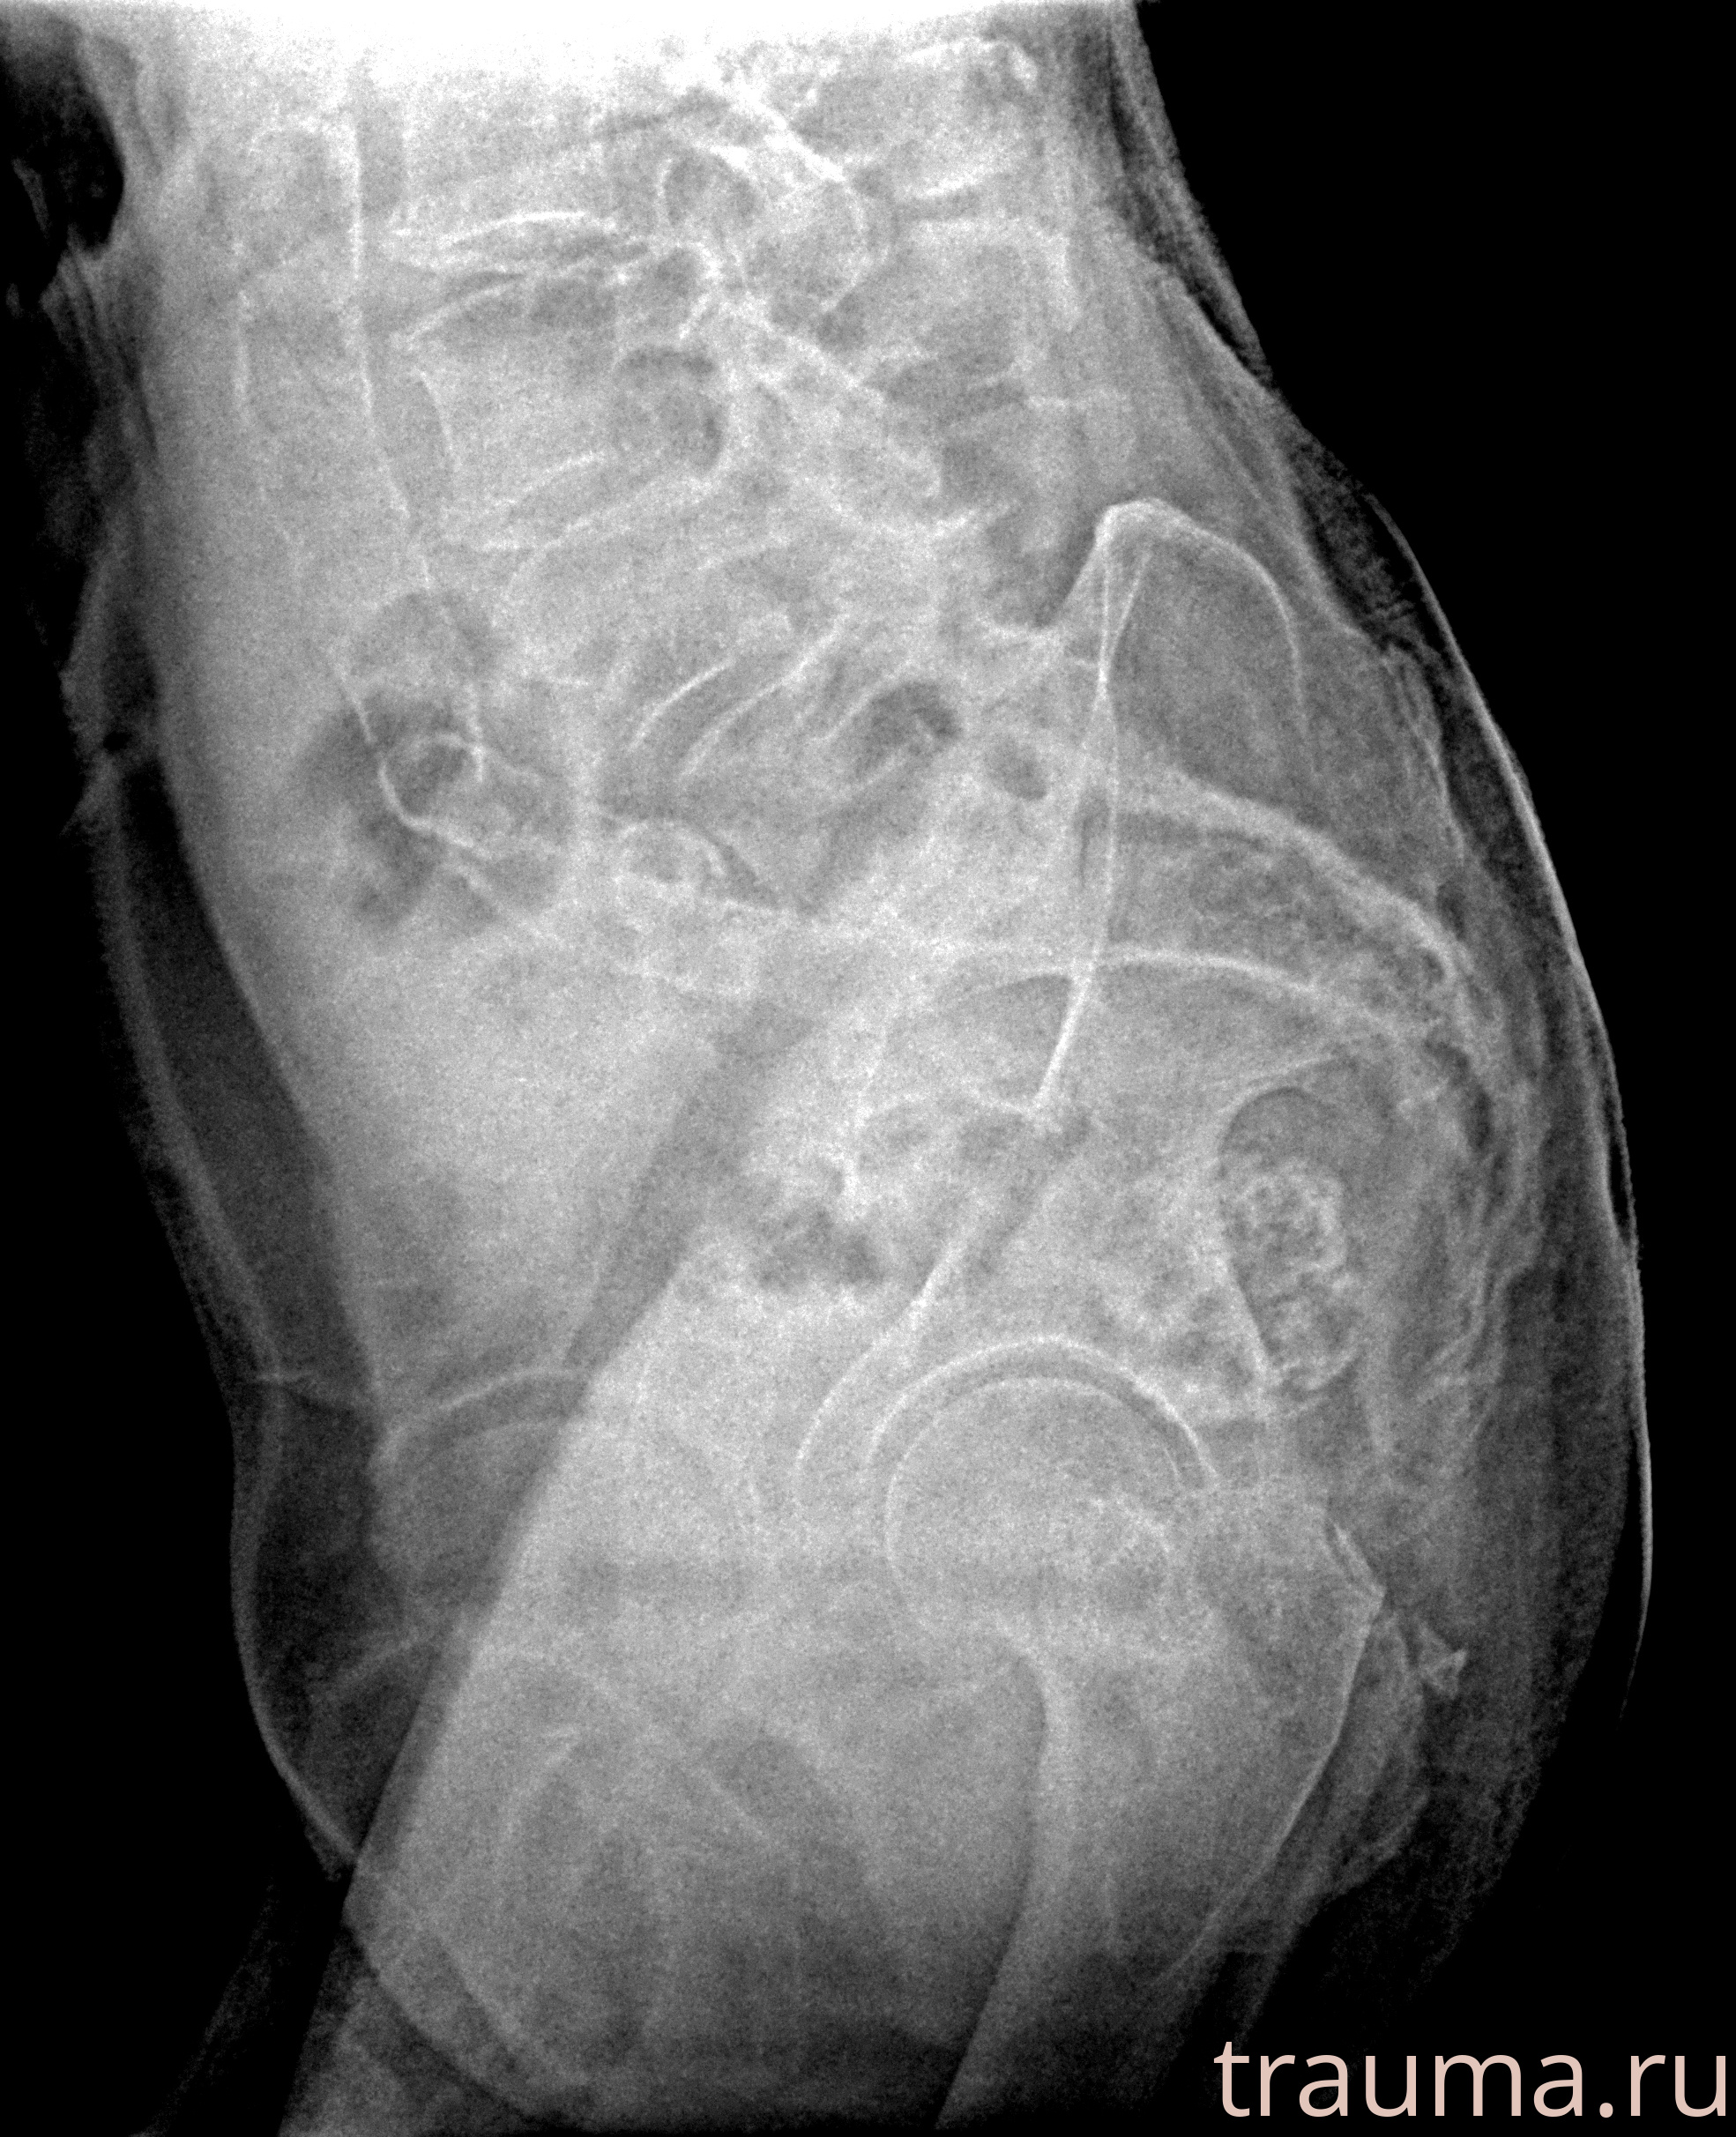

Рентгенограммы

Рентген на дому: по вашему адресу приезжает врач-рентгенолог, травматолог-ортопед с мобильным рентгеновским аппаратом, проводит диагностику травмы или заболевания, делает необходимые рентгенограммы, дает рекомендации по дальнейшему лечению. Получить качественные снимки в домашних условиях возможно благодаря уникальной методике, разработанной МосРентген Центром для института  Склифосовского

Яркость: 1   Контраст: 1   Инвертировать: 0 Увеличение: 1

Перетаскивайте мышь вверх/вниз для контраста, влево/право для яркости. Прокрутка колесом изменяет масштаб. Нажмите Сбросить для возврата к исходному изображению. При увеличении держите мышь в той области, которую хотите рассмотреть.